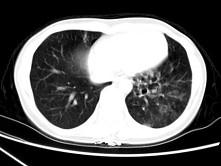

问题 女,30岁,咳痰,咯血,请结合影像图像选择最可能的诊断为 ( )

选项 A、间质性肺炎 B、肺结核 C、支气管扩张并感染 D、支气管囊肿 E、肺部感染

答案 C